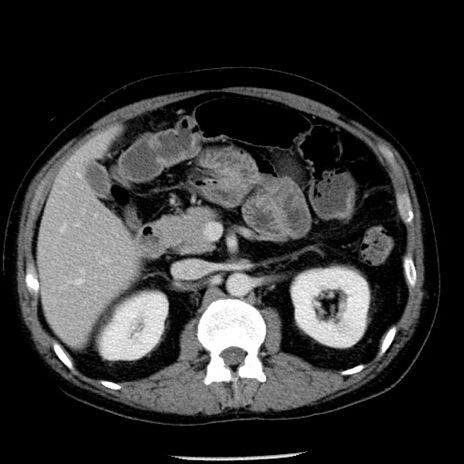

冠状断像

【症例】40歳代男性

【現病歴】2日前から胃痛あり。徐々に周期的な激痛に変化した。本日になっても激痛があるため受診。

【身体所見】意識清明、BT 38-39℃台あり、腹部:膨満、やや硬、右下腹部に圧痛あり。

【データ】WBC 8500、CRP 23.26